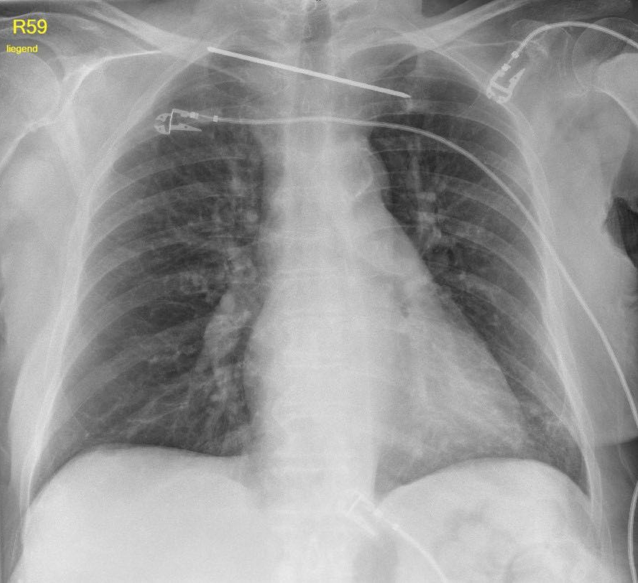

Die radiologische und klinische Verlaufskontrolle der Schulter zeigte weiterhin im Bereich der Fraktur instabile Verhältnisse. Die Patienten berichtete aber nur über leichte Einschränkungen im Alltag bei subjektivem Wohlbefinden. Über der lateralen Clavicula bestand weiterhin ein Druckschmerz. Die Muskelkraft war nicht eingeschränkt und die Sensibilität intakt. Die Bewegungsumfang im Schultergelenk betrug 120° Anteversion, 120° Abduktion und 60° Innen- und Außenrotation. Die radiologische Untersuchung zeigte die bekannte Fraktur mit verzögerter Frakturheilung (Abb. 4). Aufgrund der geringen Beschwerden, des hohen Lebensaltersalters und der bekannten Nebendiagnosen wurde von einer erneuten operativen Versorgung abgesehen. Die Patientin und deren Angehörigen stimmten dem zu. Sechs Monate nach der K‑Draht-Entfernung gibt die Patientin keine relevanten Schmerzen an und fühlt sich subjektiv wohl. Greifen und Faustschluss sind möglich. Eine leichte Einschränkung im Alltag stellt die Mobilität im Schultergelenk dar – Abduktion und Elevation sind nur bis auf Brusthöhe möglich. Mediastinale oder pulmonale Probleme bestanden nicht.

Abb. 4

Radiologische Untersuchung 4 Wochen nach der K‑Draht-Entfernung